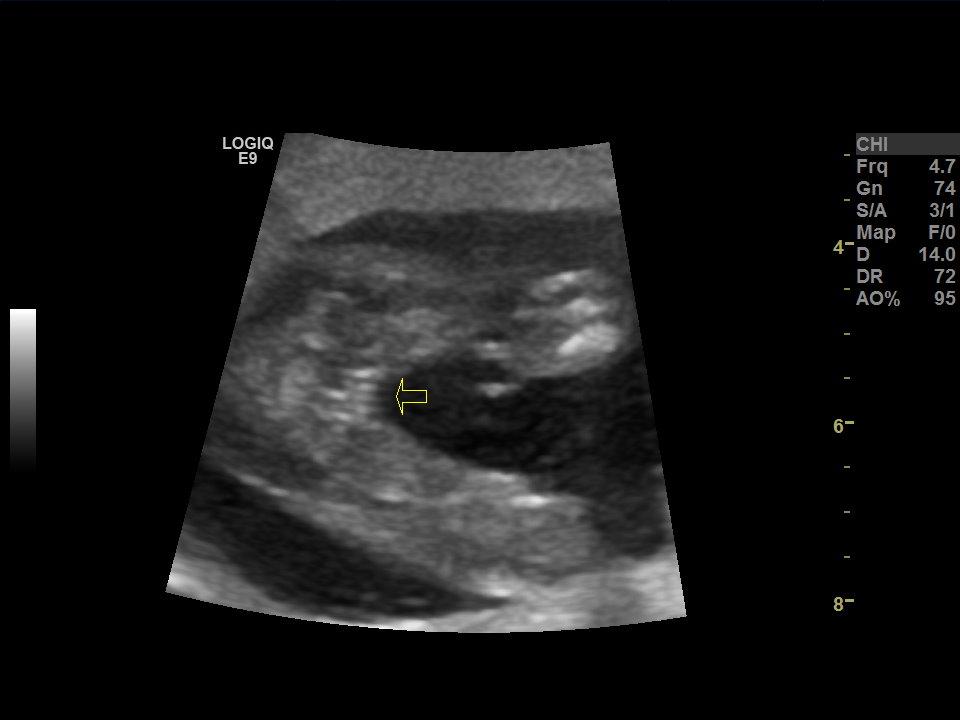

I was told girl and she said she’s very confident. I guess I’m just second guessing myself because I always hear about 3 lines but only see 2. Does it look like a girl for sure?Attachment 39231